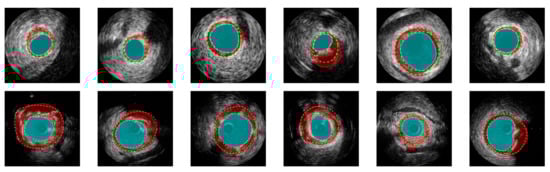

- Yang, J.; Tong, L.; Faraji, M.; Basu, A. IVUS-Net: An intravascular ultrasound segmentation network. In Proceedings of the International Conference on Smart Multimedia, Toulon, France, 24–26 August 2018; pp. 367–377. [Google Scholar]

- Yang, J.; Faraji, M.; Basu, A. Robust segmentation of arterial walls in intravascular ultrasound images using Dual Path U-Net. Ultrasonics 2019, 96, 24–33. [Google Scholar] [CrossRef] [PubMed]

- Su, S.; Hu, Z.; Lin, Q.; Hau, W.K.; Gao, Z.; Zhang, H. An artificial neural network method for lumen and media-adventitia border detection in IVUS. Comput. Med. Imaging Graph. 2017, 57, 29–39. [Google Scholar] [CrossRef]

- Balakrishna, C.; Dadashzadeh, S.; Soltaninejad, S. Automatic detection of lumen and media in the IVUS images using U-Net with VGG16 Encoder. arXiv 2018, arXiv:1806.07554. [Google Scholar]

- Bargsten, L.; Riedl, K.A.; Wissel, T.; Brunner, F.J.; Schaefers, K.; Sprenger, J.; Grass, M.; Seiffert, M.; Blankenberg, S.; Schlaefer, A. Tailored methods for segmentation of intravascular ultrasound images via convolutional neural networks. In Proceedings of the Medical Imaging 2021: Ultrasonic Imaging and Tomography, San Diego, CA, USA, 15–20 February 2021; Volume 11602, p. 1160204. [Google Scholar]

- Olender, M.L.; Athanasiou, L.S.; Michalis, L.K.; Fotiadis, D.I.; Edelman, E.R. A Domain Enriched Deep Learning Approach to Classify Atherosclerosis Using Intravascular Ultrasound Imaging. IEEE J. Sel. Top. Signal Process. 2020, 14, 1210–1220. [Google Scholar] [CrossRef] [PubMed]

- Li, Y.C.; Shen, T.Y.; Chen, C.C.; Chang, W.T.; Lee, P.Y.; Huang, C.C.J. Automatic detection of atherosclerotic plaque and calcification from intravascular ultrasound images by using deep convolutional neural networks. IEEE Trans. Ultrason. Ferroelectr. Freq. Control 2021, 68, 1762–1772. [Google Scholar] [CrossRef]